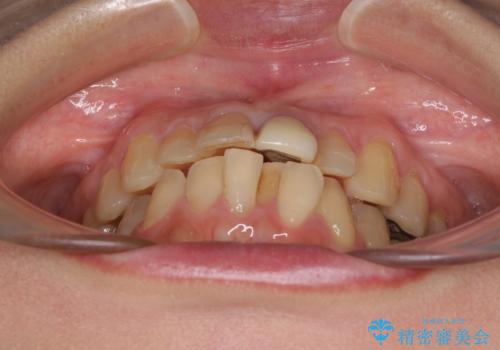

前歯のデコボコをワイヤー矯正できれいに整える

- 前歯のデコボコと変色した前歯を気にして来院された患者様です。

抜歯矯正により口元を引っ込めることも検討しましたが、特に口元の突出感は気になっていないとのことで、非抜歯にてワイヤー装置で矯正治療を行うこととしました。